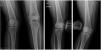

Técnica quirúrgicaMediante posición dorsal y abordaje lateral en la rodilla afecta, se llega al periostio, el cual se desperiostiza. Bajo guía de intensificador de imágenes se pasa clavo de Steiman de 3,0 de lateral a medial, pasando desde el cóndilo lateral en un ángulo de 95°, y otro clavo de Steiman a nivel supracondíleo, de manera transversal. Acto seguido se realiza osteotomía con cierre oscilante a este nivel, realizando la apertura de la misma. Se coloca placa condilar respectiva y, previa fijación de la misma, se mide el eje de la extremidad, dejando el mismo en 8° de valgo usando la torre de compresión axial de la AO (fig. 6), luego de lo cual se fija con los respectivos tornillos.

Al momento del último seguimiento presentan mejoría clínica evidente, con leve dolor en la rodilla afecta, deambulan con carga total, sin cojera a la marcha; además visualizamos radiografía de control, la cual nos muestra estabilidad del implante y osteotomía en consolidación acorde al tiempo de evolución respectivo (fig. 7).